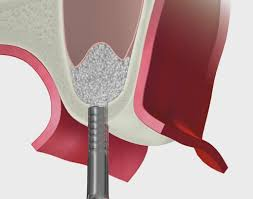

ソケットリフトの術式

口腔内の当該部位の歯肉を切開します。その後、骨を上顎洞近くまで削っていきます。この際、削る量や深さは、事前にCTにて計算しておきます。その後、オステオトームと呼ばれる先端がノミのようになった器具で上顎洞まで進めていきます。オステオトームには、ストッパーがついていますので安全に処置することが可能です。その後、必要に応じて、骨補填材を使用して、上顎洞内の粘膜を挙上していきます。インプラントを同時に埋入する場合がほとんどです。粘膜の挙上する大きさによっては、適応にならないことがあります。一般的には、浸潤麻酔のみで処置しますが、静脈内鎮静法や笑気麻酔を併用することも可能です。